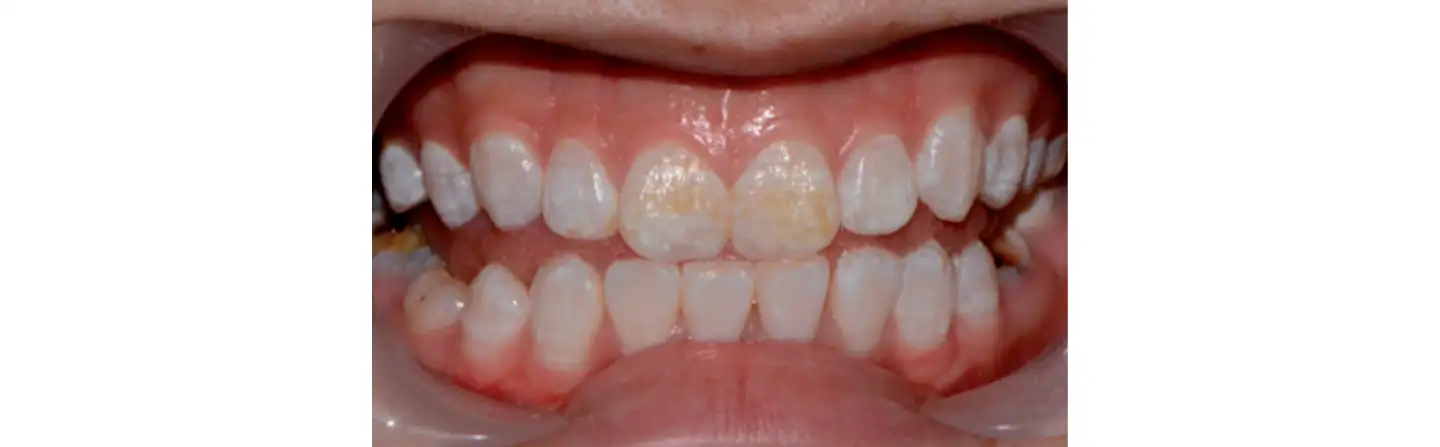

Клиническая картина после проведения микроабразии и отбеливания: